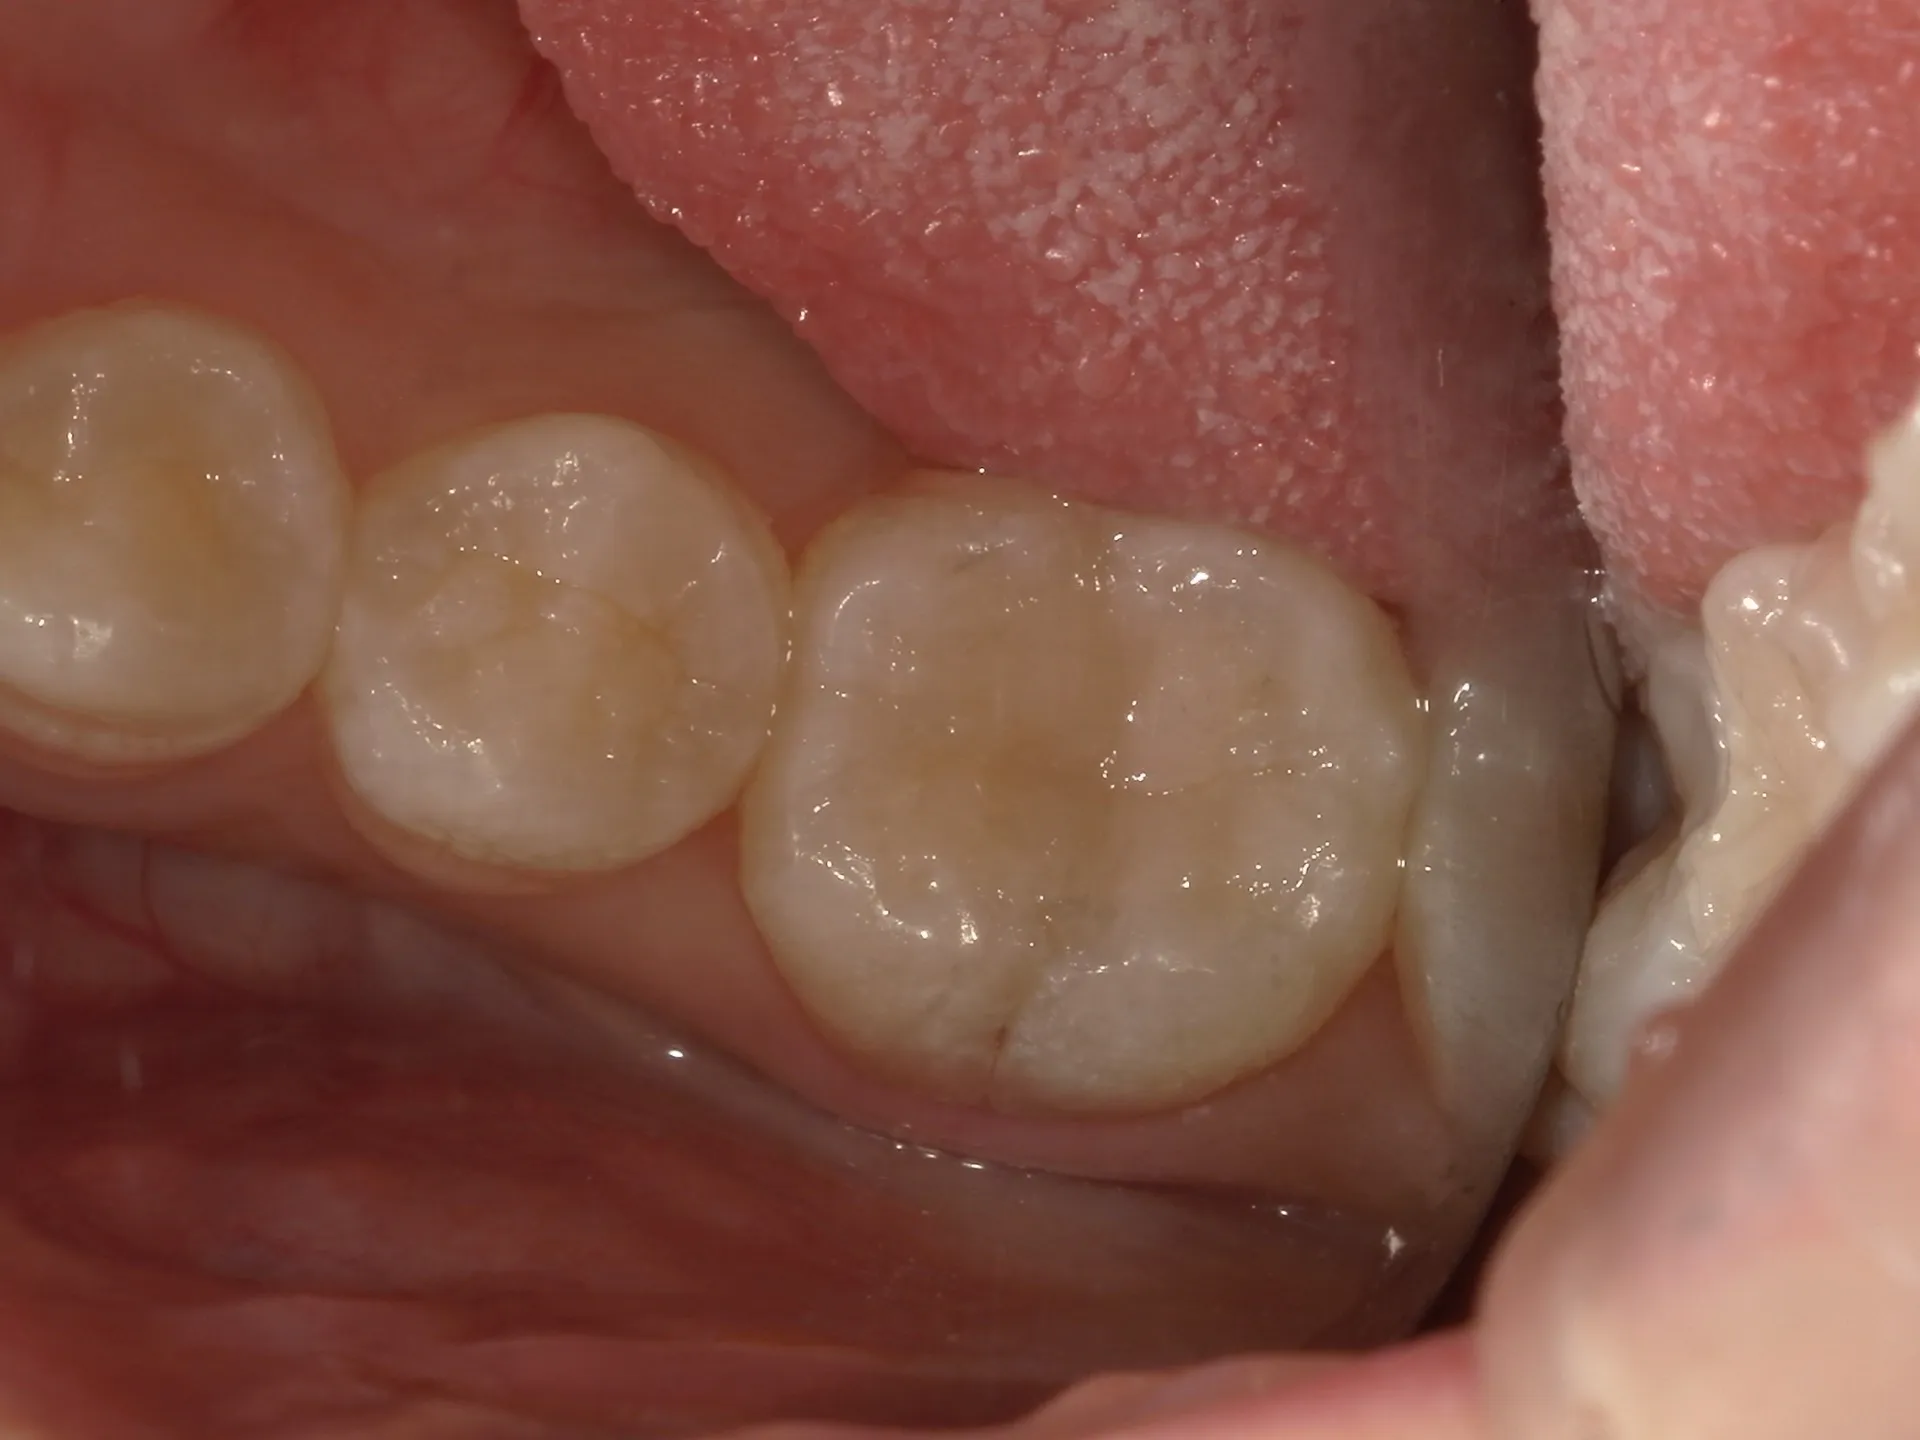

今回は一見問題なく見える歯の詰め物の下に深い虫歯があった治療の症例をご紹介いたします。